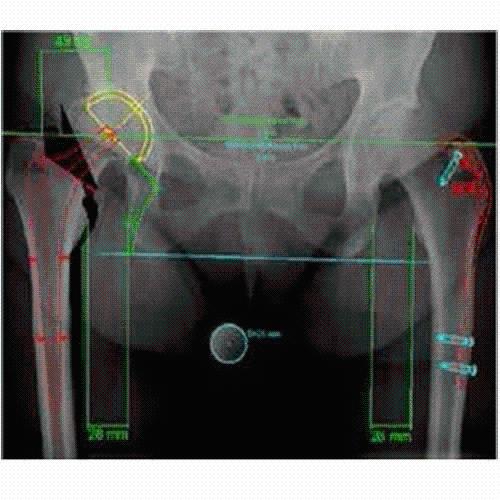

Talairach Tools

Talairach transformation is performed in two steps. The first step consists of rotating the 3D data set for each subject to be aligned with the stereotaxic axes. For this step the location of the anterior commissure (AC) and the posterior commissure (PC) as well as two rotation parameters for midsagittal alignment has to be specified interactively. In the second step the extreme points of the cerebrum are specified. These points together with the AC and PC coordinates are then used to scale the 3D data sets into the dimensions of the standard brain of the Talairach and Tournaux atlas.